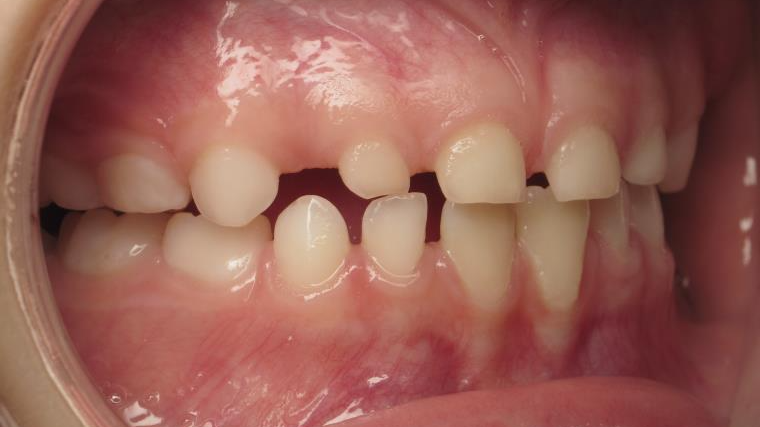

12 béance inversé droit 4 ans

inversion postérieur coté droit et espace entre les dents du haut et du bas (diastèmes)